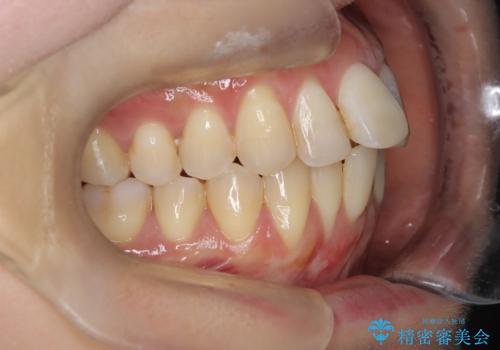

半年で改善した上顎前歯の突出

- 患者様は、上顎前歯の突出を改善したいとのご希望で来院されました。診断の結果、噛み合わせや全体的な歯列には大きな問題がないため、上顎のみを対象とした部分矯正が最適と判断しました。特に患者様は短期間での治療完了を希望されていたため、治療期間を約半年と設定しました。審美ワイヤーを用い、前歯を後方に移動させることで、自然で整った仕上がりを目指しました。治療計画は、患者様のスケジュールや希望を最大限考慮し、実現可能な目標を設定しました。

部分矯正では、治療範囲が限定されるため、力のコントロールが非常に重要です。本症例では、前歯を後方に移動させる際、周囲の歯や噛み合わせに影響を及ぼさないように細心の注意を払いました。また、短期間の治療でも歯の移動に伴う歯肉や歯根への負担を抑えるため、定期的なチェックと調整を行いました。患者様には矯正装置の清掃を徹底していただき、虫歯や歯周病のリスクを回避しました。結果として、予定通りの期間で治療を完了し、患者様には満足していただけました。